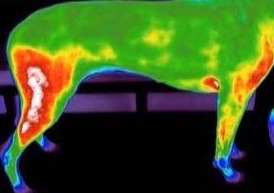

Laser and Thermography-A Complete Review

Faire des progrès avec la douleur et la boiterie - une approche holistique

Pourquoi et comment ajouter la réadaptation dans la pratique